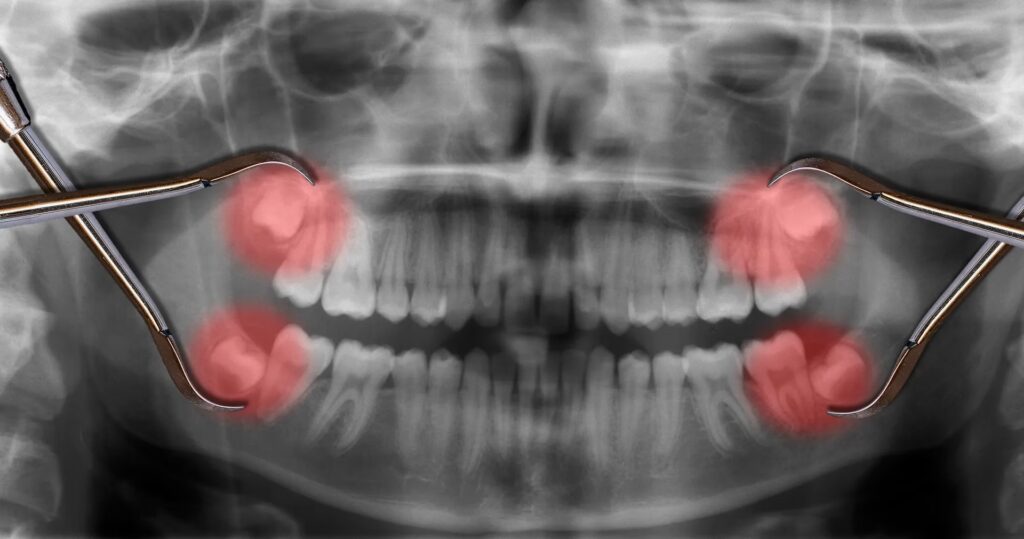

Ikke alle visdomstænder skal fjernes. Hvis de er sunde, fuldt frembrudte og korrekt placeret, kan de blive i munden resten af livet. Problemerne opstår ofte, fordi vores kæber i dag er mindre end vores forfædres, hvilket efterlader for lidt plads til disse sidste kindtænder. De mest almindelige årsager til fjernelse er:

• Impakterede tænder: En impakteret visdomstand er en tand, der sidder fast i kæben og ikke kan bryde helt frem. Den kan vokse sidelæns, i en vinkel eller forblive helt begravet i kæbeknoglen. Dette kan forårsage smerte og skade på nabotænderne.